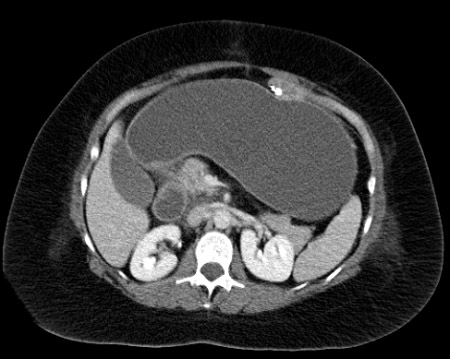

CT of the abdomen in the same patient reveals a tremendously dilated gastric remnant. With CT guidance, a dilated remnant is easily accessed percutaneously

From collection of Daniel M. Herron, MD